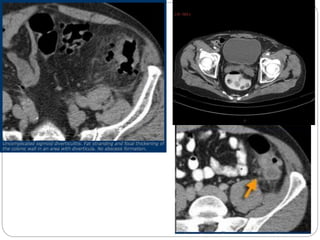

Sigmoid diverticulitis

 If the pain is located in the LLQ main concern is

In diverticulitis sonography and CT show

diverticulosis with segmental colonic wall

thickening and inflammatory changes in the fat

surrounding a diverticulum.

 Complications of diverticulitis such as abscess

formation or perforation, can best be excluded

with CT.

Diverticulitis

A case of diverticulitis showing a thickened sigmoid colon and a diverticulum